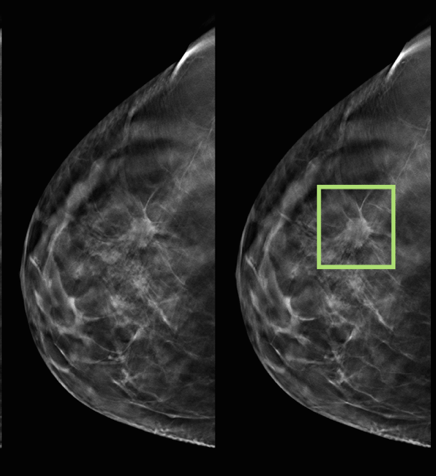

Mamografija je radiološka dijagnostička pretraga za ranu detekciju tumora dojke (nepalpabilni tumori), te za potvrdu palpabilnih tumora. Korištenjem u ranoj detekciji, momografija smanjuje smrtnost za 30%.

Preporuka je da svaka žena uradi prvi mamogram sa 45 godina (35-40 ukoliko ima pozitivnu porodičnu anamnezu). Nakon toga momografiju treba ponavljati svake 2-3 godine ili češće, ovisno o nalazima i ličnoj ili porodičnoj anamnezi.